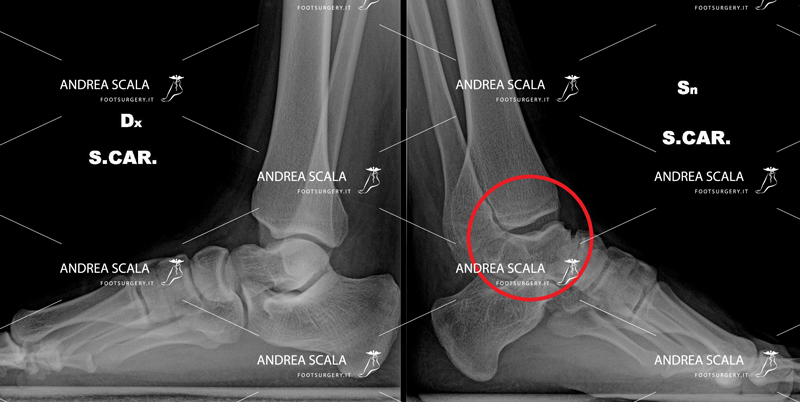

Il piede equino è dovuto alla contrazione non normale, ma patologica dei muscoli del polpaccio. Questi muscoli tirano il tendine d’Achille. Il calcagno a sua volta tirato del tendine d’Achille è sollevato dal suolo. La deambulazione del paziente viene sconvolta da questa patologia. Il piede non appoggia più la pianta ma appoggia soprattutto la punta del piede.

Questa patologia provoca a lungo andare una malformazione scheletrica e articolare della parte anteriore del piede, il quale assume una posizione del tutto innaturale. A causa del piede equino, il paziente è quindi costretto ad appoggiare a terra solo la punta del piede, tenendo sollevato il tallone. Molto spesso si associa una deviazione del piede verso l’interno (piede equino-varo-supinato) . Il piede non risulta più in asse con gambe e ginocchia.

Qualora il paziente non dovesse intraprendere subito la terapia più adatta, il piede equino potrebbe peggiorare ulteriormente arrivando a causare anche un incorregibile varismo del retropiede (la parte posteriore del piede è deviato all’interno rispetto all’asse con la gamba), instabilità della caviglia, fasciti plantari, spine calcaneari, tendinopatie e borsiti.

Al termine dello sviluppo adolescenziale di un paziente si può osservare la ricomparsa di piede equino in esiti di trattamento di un piede torto che è stato sottoposto alla terapia con gessi oppure in esiti di allungamento di tendine d’Achille. Non c’è da preoccuparsi è un quadro clinico che si può correggere.